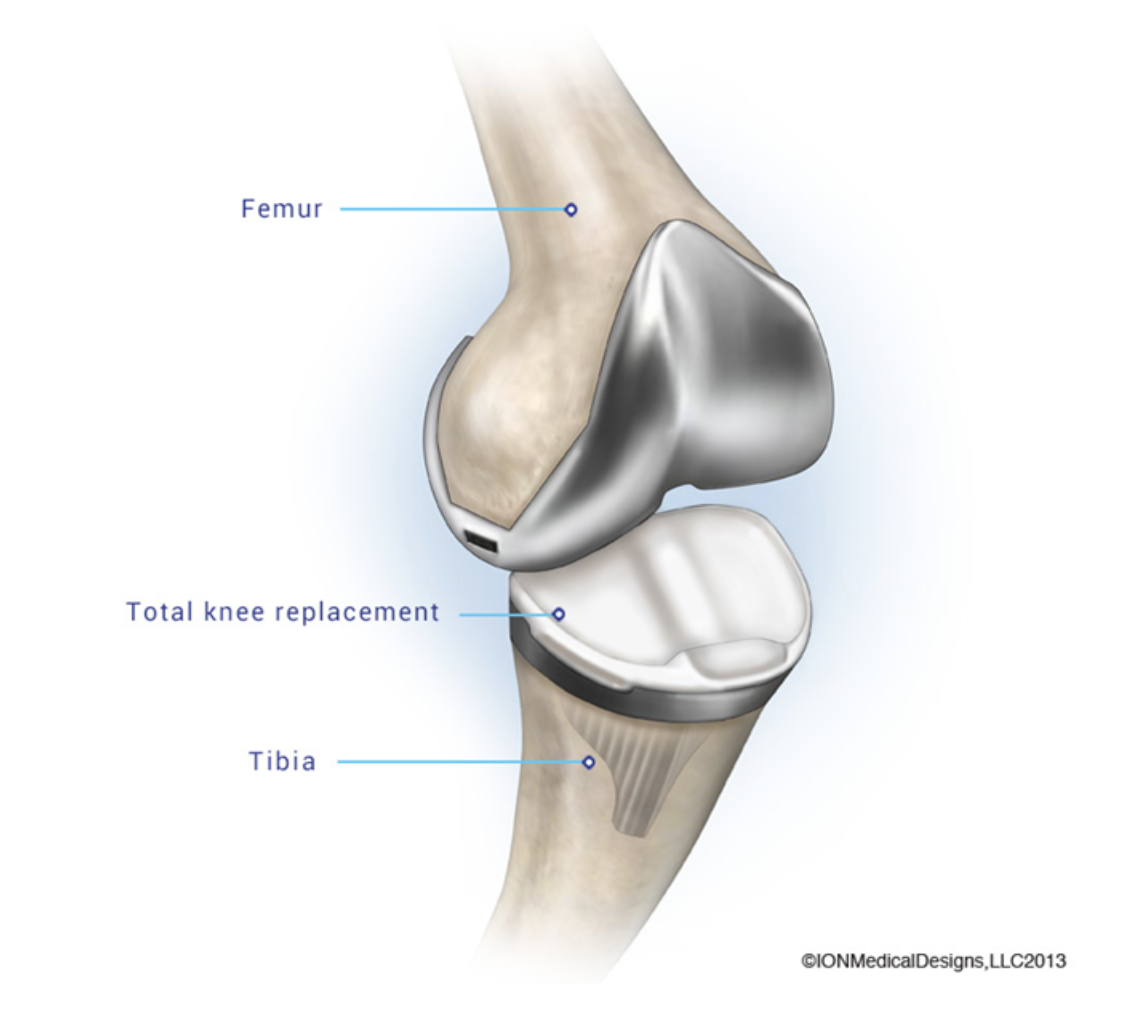

For a finite element analysis of a knee replacement, which symmetry model would be most appropriate?

- Symmetry model not possible

- One Half symmetry

- One Quarter symmetry

- One Eight symmetry

Symmetry model not possible